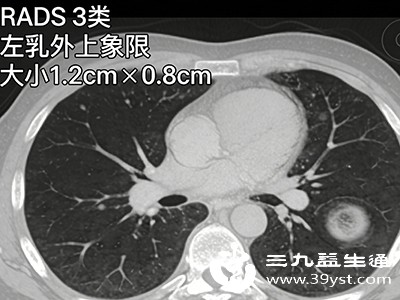

除了上述常见的检查部位,还有一些特殊部位的彩超检查。例如甲状腺、乳腺彩超,这些部位远离胃肠道,检查时不会受到进食的影响,无需空腹,正常进行检查即可。而对于一些特殊情况,如怀疑腹部有占位性病变,但病变位置不明确,可能需要进行全腹部的详细检查,此时也需要遵循空腹的要求,以确保整个腹部器官都能清晰显示,避免因胃肠干扰而漏诊。